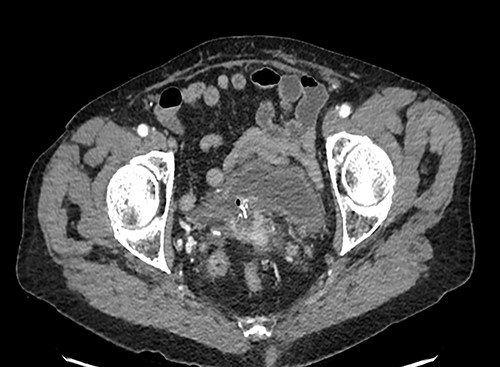

A 90-year-old woman presented with abdominal pain and pneumaturia; in her medical history we find a laparotomy mesh rectopexy 15 years ago. CT scan showed inflammation around the mesh that can also be seen entering the bladder (Figs 5 and 6).

While cystoscopy showed the presence of the mesh in the urinary bladder, rectoscopy visualized the mesh on the anterior wall of the rectum at 3 cm from the anal marge.